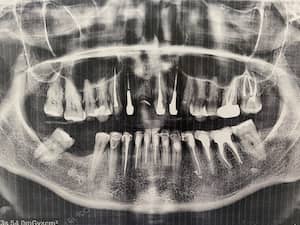

До

После

Удаление 7 зубов, установка 11 имплантов Straumann, временное и постоянное протезирование всех зубов с учетом формы, цвета и размера зубов. Работа с мягкими тканями. Импланты использовались для немедленной нагрузки.